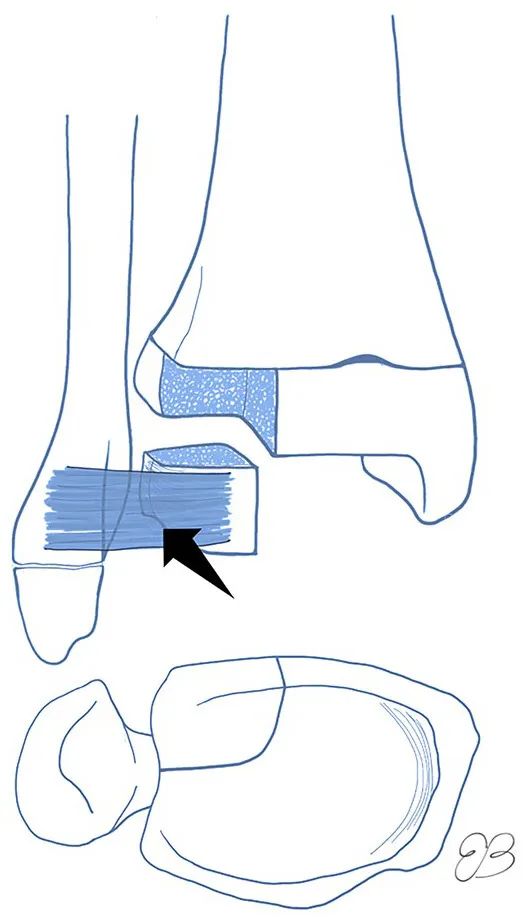

胫骨远端骨骺闭合的顺序。闭合从前内侧区域 (A) 开始,然后向内侧 (B)、后侧(C)和外侧(D)进行。图源:DOI: 10.1302/2058-5241.6.200042.